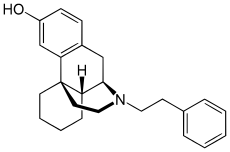

Morphinans

Morphinan series

- Phenomorphan

Structures

| Other morphinans | ||||

Phenomorphan Phenomorphan |